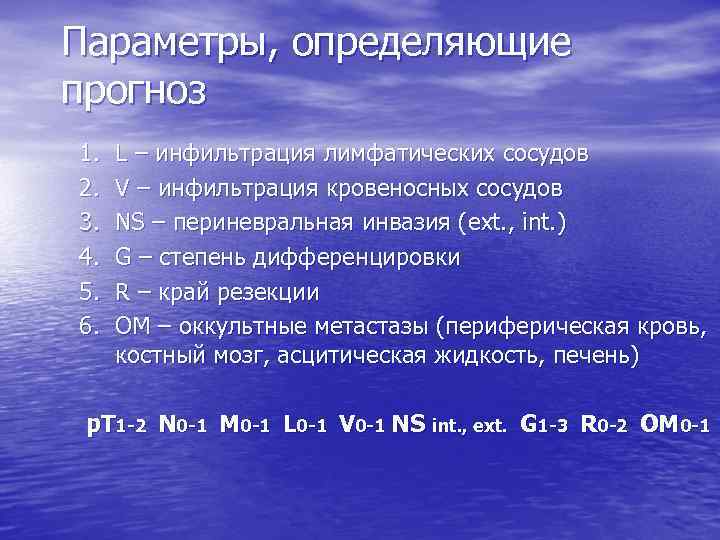

Параметры, определяющие прогноз 1. 2. 3. 4. 5. 6. L – инфильтрация лимфатических сосудов V – инфильтрация кровеносных сосудов NS – периневральная инвазия (ext. , int. ) G – степень дифференцировки R – край резекции OM – оккультные метастазы (периферическая кровь, костный мозг, асцитическая жидкость, печень) p. T 1 -2 N 0 -1 M 0 -1 L 0 -1 V 0 -1 NS int. , ext. G 1 -3 R 0 -2 OM 0 -1